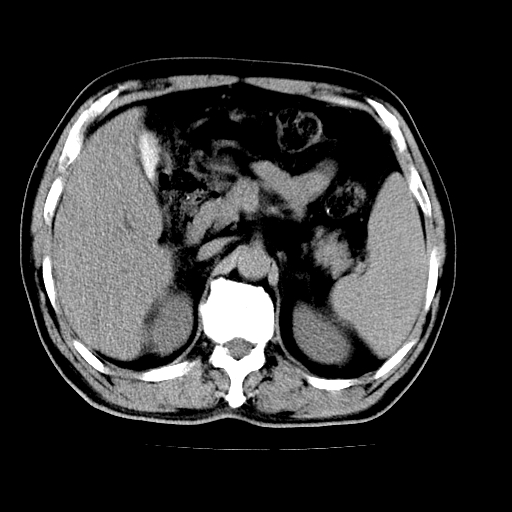

男,66岁,上腹部不适、黄染一周。彩超示:肝左叶占位,肝内胆管扩张,胆总管扩张,胆总管占位?

肝左叶不规则软组织肿块影,边缘不规整邻近肝实质受累分界不清;肝内胆管(左叶)明显扩张成“软藤状”,诊断:肝左叶胆管细胞癌。

肝左叶占位性病变,并胆管扩张,符合胆管细胞癌ct表现,门脉左支受累,左肾囊肿。窗宽太窄了,其他的看不清

左叶胆管细胞癌累及胆总管,门脉左支受侵,慢性胆囊炎胆结石,左肾小囊肿

肝左叶不规则软组织肿块影,边缘不规整邻近肝实质受累分界不清;肝内胆管(左叶)明显扩张成“软藤状”,诊断:肝左叶胆管细胞癌。胆囊钙乳症。